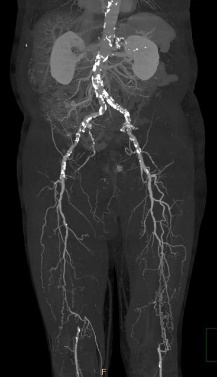

Image

Contrast enhanced MR angiography"

Fig. 22. Left sided segmental occlusion at the iliofemoral segment

CT angiography

Fig. 23. Bilateral superficial femoral artery occlusion with collateral filling

Multi-slice CT is able to perform CT angiography scans that map the body from the diaphragm to the ankles depicting the complete arterial tree with adequate intensity and with appropriate spatial resolution. In most cases this has a sufficing diagnostic value and it is especially advantageous for the rapid assessment of patients in poor condition. For the MRA of this wide region a special table toggling technique is required. This method applies prolonged injection of intravenous bolus contrast medium, and in three table-toggling steps it can visualize the arterial system of the abdominal aorta and the peripheral arteries up to the ankle with an acceptable spatial resolution. MRA examinations has the best diagnostic value for lesions presenting at the aortoiliac and femoropopliteal regions in cases with a relatively limited extension and a reasonable severity. CTA examination (with specific contrast injection protocol) provides better spatial resolution tough even in this region starting to replace angiography as a first choice of examination in the diagnostics of acute coronary syndromes.